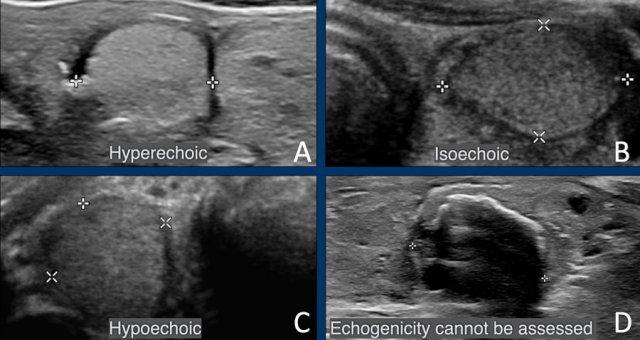

Echogenicity

Tổn thương tăng âm và đồng âm

Cả tổn thương tăng âm và đồng âm đều được tính 1 điểm trong hệ thống phân loại TI-RADS. Về mặt tính điểm, không có sự phân biệt giữa hai loại này.

Độ hồi âm được đánh giá so với nhu mô tuyến giáp bình thường.

Tổn thương giảm âm

Tổn thương giảm âm có độ hồi âm thấp hơn so với nhu mô tuyến giáp bình thường xung quanh.

Nếu không thể đánh giá chính xác độ hồi âm (ví dụ: do sự hiện diện của các vôi hóa), mặc định sẽ được tính 1 điểm.

Tổn Thương Giảm Âm Rõ Rệt

Tổn thương giảm âm rõ rệt có độ hồi âm thấp hơn so với mô cơ bình thường.

Lưu ý rằng, trong hình ảnh được cung cấp, tổn thương có độ giảm âm cao hơn so với các cơ dải (được chỉ bởi các mũi tên).